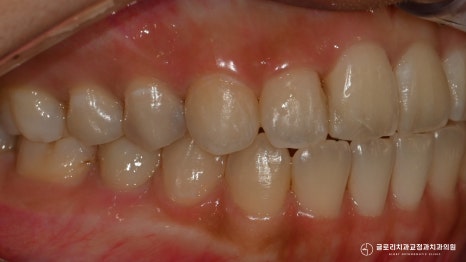

초진 사진을 보면 우측 상악 앞니 한 곳이

옆으로 틀어져 있는 듯한 모습이 관찰되었는데요.

이외에는 눈에 띄는 문제를 찾을 수 없을 정도로

정중선도 잘 맞고 있었으며

교합도 정상 범주에 속해 올바르게 맞물리고 있었죠.

수직 피개량이 약간 아쉽긴 했지만

다행히 음식을 끊거나 생활을 할 때

불편함이 없다는 말씀을 해주셨습니다.

어금니 교합도 1치대 2치대로 잘 맞고 있네요.